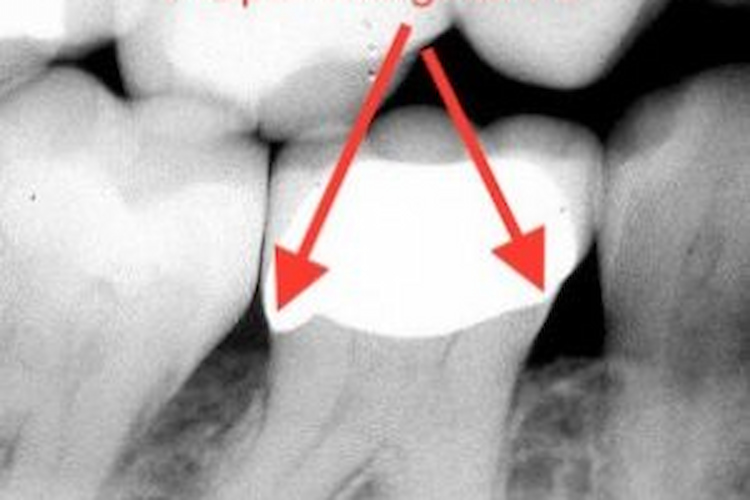

Why overhanging margins are a concern

When a crown has an overhang, it creates a microscopic ledge where bacteria can easily accumulate. Patients often cannot clean this area effectively at home, even with proper brushing and flossing.

Over time, this leads to:

- Plaque buildup that hardens into tartar

- Gum irritation and inflammation

- Increased bacterial activity around the tooth

- Higher risk of secondary decay under the crown